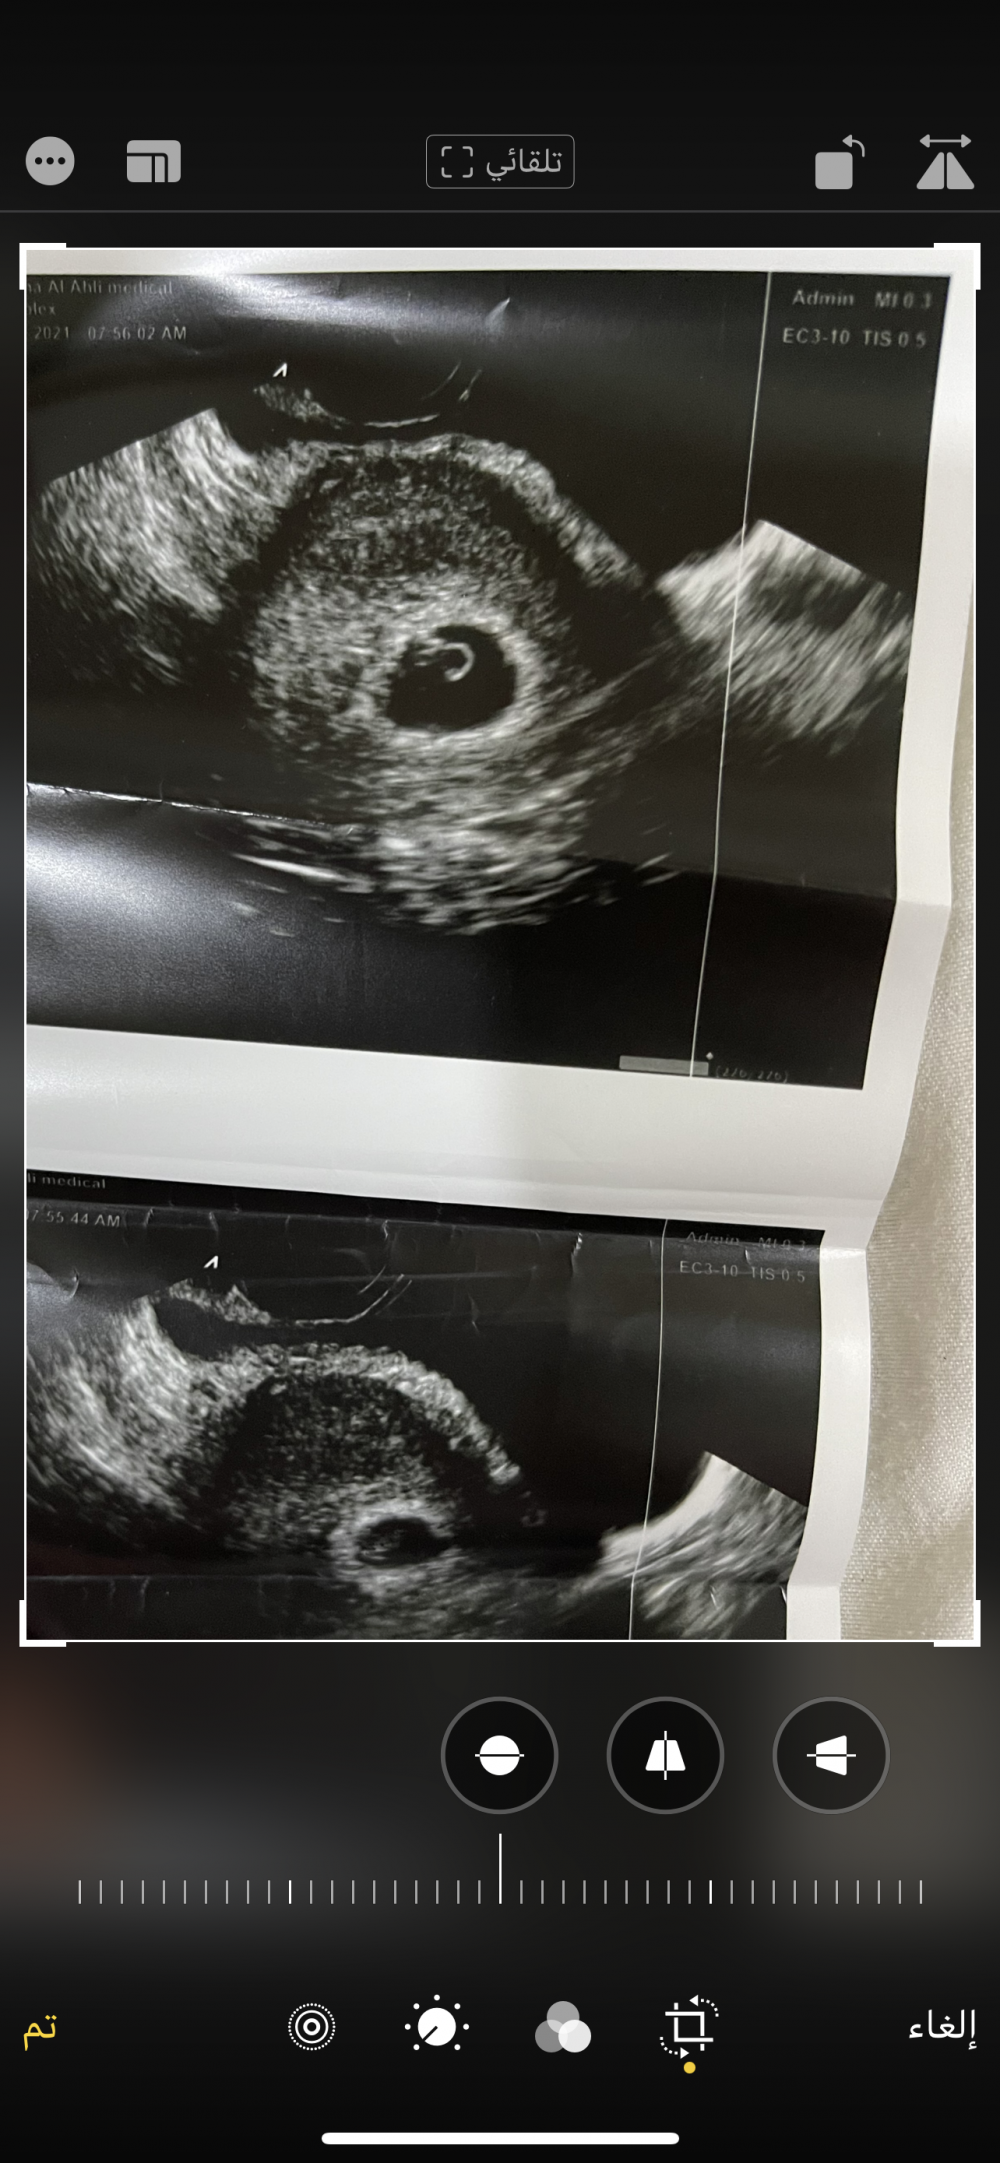

هذا في الاسبوع السادس